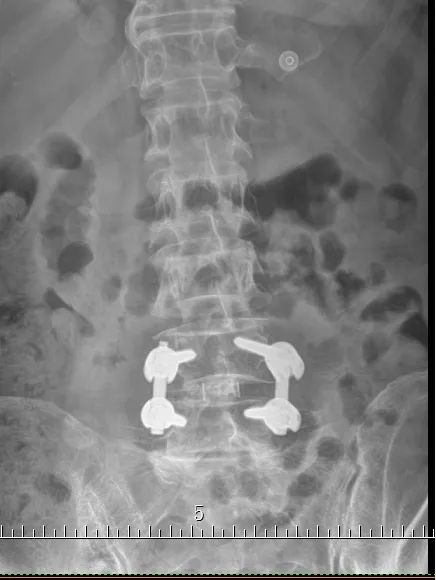

术后X光片

考虑到老伯已是82岁高龄,医院为他实施了经椎间孔入路的微创腰4/5椎管减压、椎间盘摘除,植骨融合内固定手术(mis-TLIF)。手术过程非常顺利,术中仅有少量的出血。术后第二天老伯就能自主翻身,第三天在腰围的保护和家人的协助下,就能缓慢起坐。术后第五天,老伯就开始在医护人员的协助下下地行走了。原先的腿痛几乎完全消失,走路时腰也挺直了。